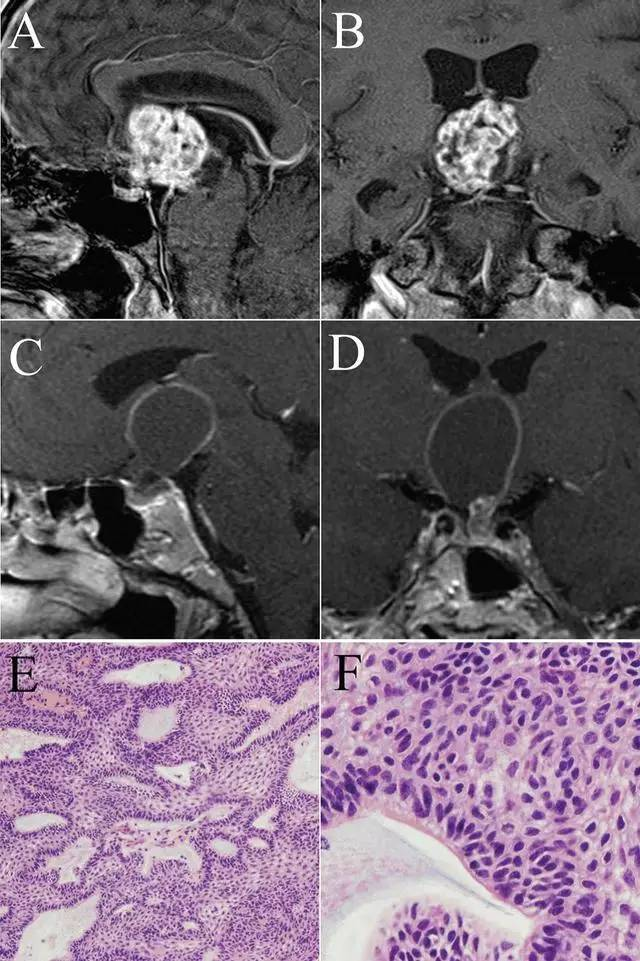

颅咽管瘤,曾因其组织学特征和发生部位有过不少名称:釉质瘤、表皮瘤、髓样癌、Rathke肿瘤和Rathke囊肿病、垂体管肿瘤、颅咽管囊肿瘤以及垂体柄肿瘤等,直到1930年Mclean提出颅咽管瘤的命名方才沿用至今。Rathke囊肿又称垂体胶样囊肿、垂体囊肿、上皮黏液囊肿、上皮样囊肿等。显然,命名上两者就有很多相似之处。

从组织来源上溯源,垂体发育自口咽膜外胚层的Rathke囊和前脑泡神经垂体芽。胚胎早期,颅咽管和Rathke囊是同时存在的,Rathke囊包括颅咽管瘤,颅咽管瘤只是Rathke囊一部分,但两者大约于胚胎11周时消失。颅咽管发育残留细胞发生突变而产生颅咽管瘤,因其来自口咽膜外胚层,因此易出现与骨化相关的钙化。Rathke囊袋前壁和后壁两者之间有部分成人残留一小腔隙,该腔隙在大多数成人逐渐被上皮细胞内折所填充,但部分成人该腔隙可一直保留下来。当腔隙内分泌物增加,腔隙明显扩张时可形成Rathke囊肿。

因此颅咽管、Rathke囊都源自垂体的胚胎发育过程。颅咽管瘤的出现类似于畸胎瘤的存在,是垂体的胚胎发育残留细胞发生突变而产生的良性肿瘤。Rathke囊肿只是Rathke囊袋前壁和后壁之间残留的腔隙,系垂体胚胎发育不完全的产物。

综上所述,颅咽管瘤和Rathke囊肿虽组织发生同源,但发生机制、发病过程、临床特点以及影像学表现等均大相径庭,了解这些特点有助于医师在临床工作中进行鉴别诊断,减少误诊。